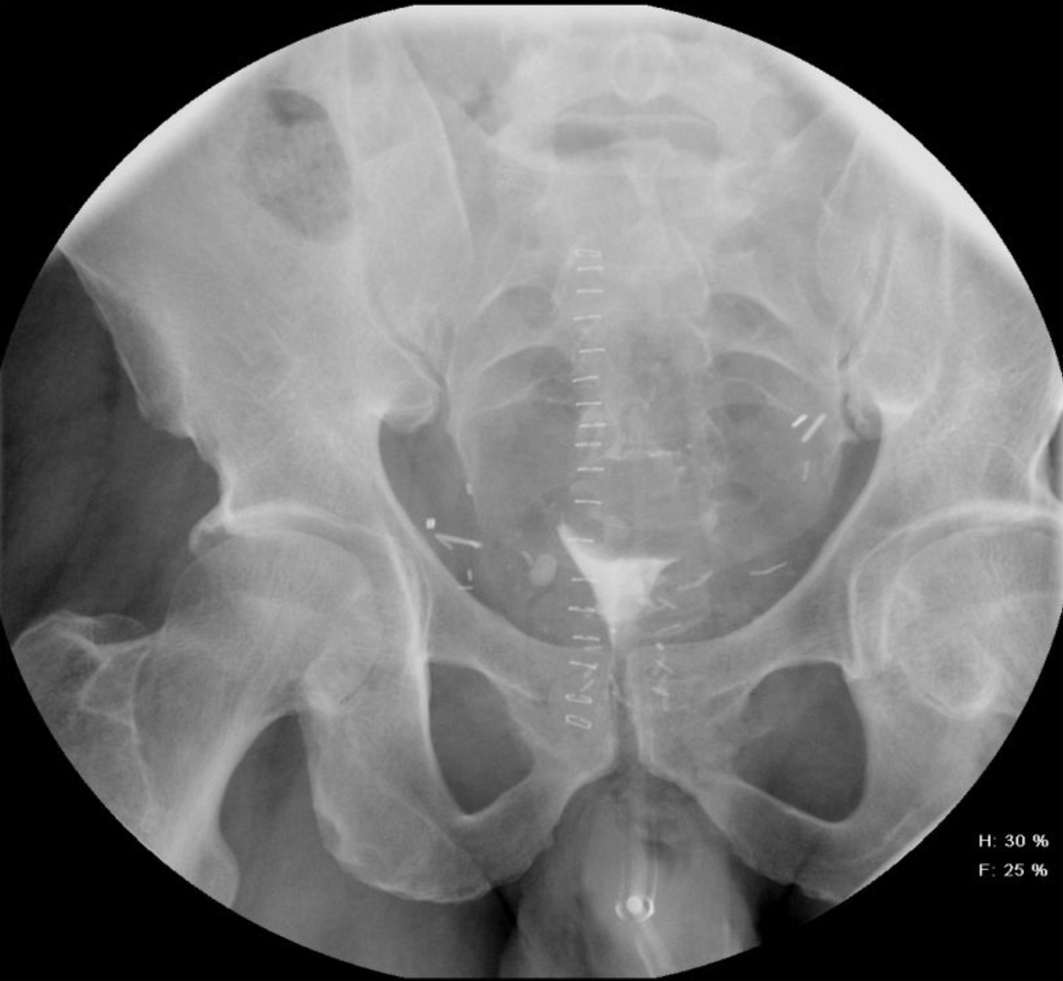

A 54-year-old African American male, presented to our facility with a prostate specific antigen (PSA) of 5.8 ng/mL. Prostate biopsy revealed three cores of Gleason 6 adenocarcinoma. On digital rectal examination he was found to have an approximately 60 g prostate, which was firm and smooth. He underwent an open retropubic radical prostatectomy (RRP). The pathologic specimen showed Gleason 7 adenocarcinoma occupying 20% of the specimen. The stage was T1cN0M0. On the fourth post-operative day, the patient presented to the Emergency Department in another facility complaining of chest pain and shortness of breath. A clinical diagnosis of pulmonary embolism (PE) was made and he was treated with a full dose of IV heparin. He subsequently developed hematuria and complained of lower abdominal pain. On physical exam, he was found to be pale, with diffuse abdominal tenderness, guarding and tachycardia. The patient was then transferred to the Surgical Intensive Care Unit (SICU) at our facility. He received two units of packed red cells. A cystogram showed complete disruption of the UVA with displacement of the bladder neck in the left upper quadrant of the abdomen producing a “pie in the sky” appearance. However, there was no evidence of urinary extravasation indicating an intact bladder neck (Fig. 1, 2). A CT scan revealed a very large pelvic hematoma displacing the bladder neck towards the left upper quadrant (Fig. 3). An IVC filter was inserted to prevent migration of thrombi so that he could discontinue the use of anticoagulants. Patient was managed conservatively for 6 - 8 weeks with gentle traction, and this helped maintaining the bladder neck within the pelvis. A cystogram showed no extravasation of urine. The Foley catheter was removed. The patient voided well initially; however, he developed bladder neck contracture (BNC) after 2 weeks. He was managed with dilation of the bladder neck, but the bladder neck did not return to the pelvis. It was found to be 2 cm away from the urethra, and a “pseudo-tunnel” made of scar tissue was seen between the true bladder neck and the membranous urethra. A surgical approach was used to explore the patient and the “pseudo-tunnel” was resected. Re-anastomosis of the bladder neck with the urethra was performed. The patient has remained continent since then and voids with minimal post void residual urine. There has been no recurrence of BNC (Fig. 4, 5). He needs intra-cavernous injections to help with erections. His post-operative PSA has remained undetectable.

![]() Click for large image | Figure 2. Showing significant displacement of the bladder neck (oblique view). |